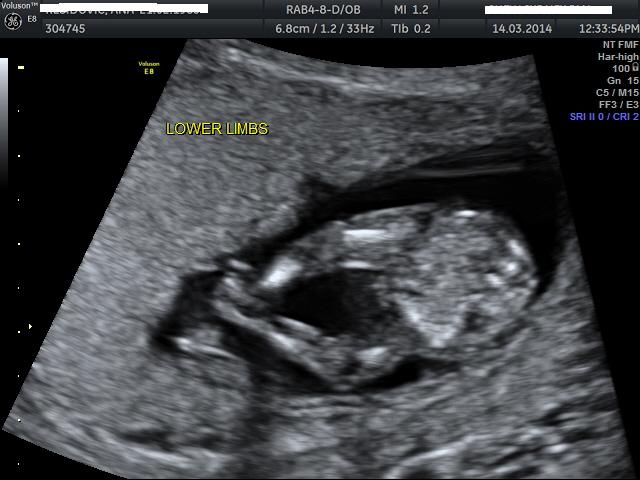

12weeks + 6 days